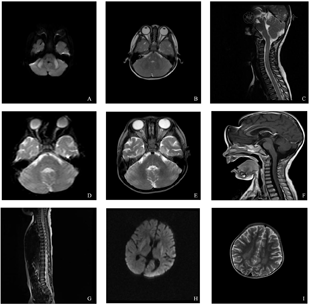

辅助检查:血尿串联质谱分析检查未发现血氨基酸、酰基肉碱,尿有机酸等异常;脑脊液常规、生化和病原学检测未见异常,寡克隆条带阴性;自体免疫性脑炎多项抗体阴性,血清乳酸正常。入院时头颅及脊髓磁共振成像(magnetic resonance imaging,MRI)可见两侧小脑中脚及小脑半球对称性斑片状异常信号,T1加权像呈低信号,T2加权像稍高信号,DWI呈高信号,增强扫描病灶未见强化。颈段、胸段脊髓广泛肿胀,信号异常,T1加权像呈低信号,T2加权像呈稍高信号,增强扫描病灶未见强化(图2A、图2B、图2C)。脑电图显示中度异常脑电图(睡眠期:未见明显痫样活动及局灶性改变;异常波:见多量阵发性,弥漫性,高电位2.5c/s δ活动)。病程1个月头颅及脊髓MRI显示两侧脑室偏大、两侧额颞脑沟偏深;增强后两侧颞底脑膜强化,颈部、胸部脊髓病灶消失(图2D、图2E、图2F)。全外显子及线粒体基因组高通量测序发现,患儿NAXE基因(NM_144772.3)携带纯合突变c.733A>C,p.Lys245Gln,经Sanger测序家系验证父母为该突变的杂合携带者,判断为与目前临床症状相关的主要致病性突变,患儿确诊为LS。

病例1入院时头颅和脊髓MRI显示两侧小脑中脚及小脑半球对称性斑片状异常信号:A.DWI呈高信号;B.T2加权像呈稍高信号;C.颈段、胸段脊髓广泛肿胀伴信号异常,T2加权像呈稍高信号;D~F.病程1个月后小脑(D、E)和颈段(F)异常信号消失,两侧颞底脑膜强化。病例2 26月龄时头颅和脊髓MRI显示双侧尾状核头部、双侧豆状核、双侧侧脑室体部旁白质及左侧枕顶叶多发片状异常信号:G.颈髓及上胸段稍肿胀,T2加权像呈稍高信号;H.DWI呈高信号;I.T2加权像呈稍高信号。

26月龄:"精神萎靡1周余,发热3 d,面肌抽动半天"入院。入院体检:神志不清,仅对疼痛刺激有反应,面肌抽动,肌力、肌张力低下,腹壁反射未引出,提睾反射未引出,双侧上下肢深反射减弱,病理征(-),颈部抵抗感,布氏征(-),克氏征(-)。头颅和脊髓MRI提示双侧侧脑室后角周围脑白质减少,颈髓及上胸段肿胀、T2W稍高信号(图2G)。血乳酸0.5 mmol/L。入院当天出现持续高热伴抽搐,呼吸暂停,口唇青紫等,给予气管插管,甲强龙冲击和维持治疗,IVIG支持,左乙拉西坦和丙戊酸抗惊厥,阿昔洛韦抗病毒,预防性抗生素应用,降颅压等治疗,5 d后撤机,治疗2周好转出院。

27月龄:以"双手和头部震颤,反应和眼球运动迟钝、发音含糊3 d"入院。入院体检:神志清,反应迟钝,眼球不能跟随物体运动,双瞳孔等大等圆,对光灵敏,双手震颤,能扶站,不能行走。上肢肌力Ⅳ级,下肢肌力Ⅲ级,双膝腱反射存在,巴氏征(-),颈部强直,布氏征(-),克氏征(-)。头颅MRI平扫:双侧尾状核头部、豆状核和侧脑室体部旁白质及左侧枕顶叶多发片状异常信号,DWI呈高信号,T2加权像呈稍高信号;各脑池及脑沟略扩大,双侧侧脑室稍大(图2H、图2I)。视频脑电图:弥漫性高波幅慢波持续发放,双侧额颞区大量痫样放电,暴发-抑制;血乳酸波动于2.0~5.7 mmol/L;横纹肌活检病理标本未发现明显异常。入院后2 d出现反复发热,3 d出现昏迷,颈强直,不自主咀嚼动作,震颤加重,呼吸不规则,口唇青紫,给予气管插管,甲强龙冲击和维持,IVIG支持,预防性抗生素应用,降颅压,抗惊厥,稳定内环境等治疗,患儿意识障碍进行性加重,对外界刺激无反应,无自主呼吸,并相继出现中枢性尿崩、高血糖、循环不稳定、瞳孔散大固定等严重脑功能损伤,住院4周撤离呼吸机死亡。

报道NAXE变异导致LS相关病例的文献极少[5,6,7,8,9,10]。大部分患者在发病前(生后2年内)神经和运动发育正常,发病后通常出现神经系统病变和自发好转/改善的波浪形病程,多数在儿童早期(6岁之前)死亡。多数患者,包括本研究报道的2例患儿,神经系统症状和进展由发热/感染诱发,而起病年龄较大的患者可由乙醇和(或)四氢大麻酚引起[5]。几乎所有患者在临床过程中出现神经运动障碍(包括共济失调、眼球震颤、斜视、流涎、肌力下降,肌张力障碍和震颤)、反复呼吸功能不全/衰竭和间歇性昏迷,部分癫痫发作,与所涉及的线粒体功能障碍相关。极少部分病例表型相对较轻,发病年龄较晚(20岁以上),病程较长(4~7年以上随访中)。有影像学报道的病例中[5,6,7,8,9,10],大部分可发现不同神经系统部位的对称性病变,包括脑水肿、脑萎缩、脑坏死、小脑水肿、脊髓病变和白质脑病等,有1例表现为类似于神经发育障碍的巨脑回。然而同一患者在疾病发作不同时期,颅脑和脊髓MRI影像学检查可出现较大差异。如本研究病例2以波浪性渐进性病程为特征,临床症状以亚急性起病、迅速进展和自发缓解为特点;但颅脑影像学检查最初正常,随疾病发展,重复MRI扫描显示颅脑和脊髓多发异常信号,最终因昏迷而死亡。而病例1以急性起病,间歇缓解为特征,起病后迅速出现呼吸衰竭、昏迷和运动障碍;颅脑和脊髓影像学病变显著,随着疾病严重度的缓解,颅脑和脊髓影像学病变信号也随之消失。本病也可累及神经系统以外的组织和器官,如皮肤和肾脏等。为了阐明NAXE突变的完整临床谱,期待更多相关病例报道。